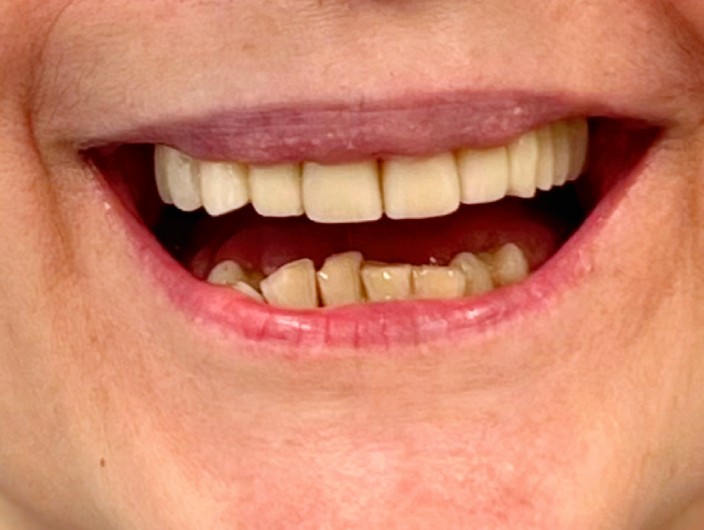

Piękny uśmiech to nie tylko kwestia estetyki, ale także zdrowia i samopoczucia. W naszej klinice stomatologicznej specjalizujemy się w przeprowadzaniu spektakularnych metamorfoz, które nie tylko transformują uśmiechy, ale również zmieniają życie naszych pacjentów. Przyjrzyjmy się bliżej tym niesamowitym przemianom i technologiom, które je umożliwiają.

Zaprezentujemy serię poruszających historii pacjentów, którzy zdecydowali się na kompleksowe leczenie dentystyczne. Od przypadków zaawansowanej próchnicy, przez wypadki, które wymagały rekonstrukcji zębów, po pacjentów marzących o hollywoodzkim uśmiechu dzięki zastosowaniu licówek – każda historia jest dowodem na to, jak nowoczesna stomatologia może odmienić życie.